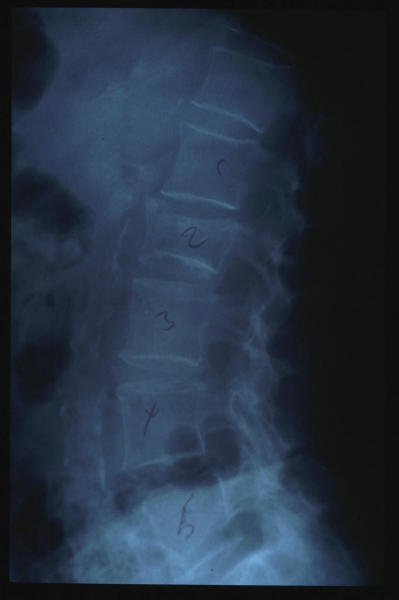

Osteoporosis. Cifosis.